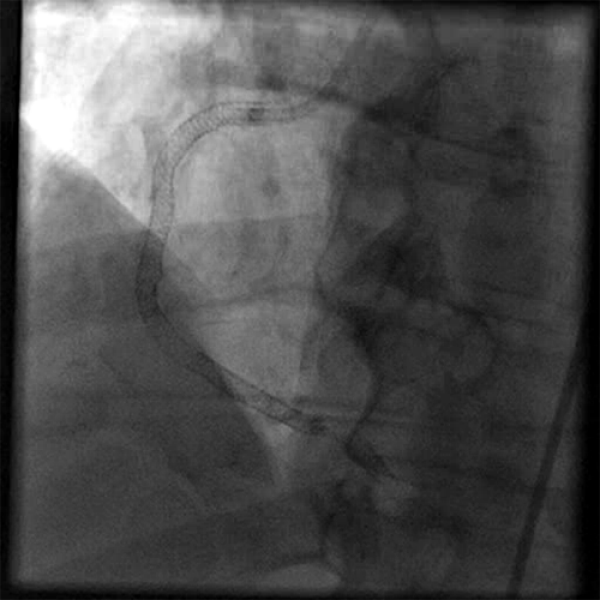

Occasional ventricular arrhythmias and even sudden cardiac death have been reported.įigure 1: Measurement of coronary flow by CTFC.

III - Pro gnosisĬoronary slow-flow phenomenon usually has a benign long term outcome but may be associated with relapses. Nitric oxide potentiating β-blocker nebivolol improved flow mediated dilatation of brachial artery and controlled chest pain in a study conducted by Albayrak et al ( 10). Statins with their pleiotropic effects on the vascular function have shown benefit in the treatment of CSFP ( 9). In an observational study, Kurtoglu et al found dypiridamole to be useful in the management of CSFP, with symptomatic as well as angiographic improvement ( 8). The data on conventional L-type calcium channel blockers use is scarce. However, due to its many drug to drug interactions, mibefradil is currently not in use. The T -type calcium channel blocker mibefradil was evaluated and was found to improve both clinical as well as angiographic outcomes ( 7). Treatment modalities for CSFP are not well established. There are case reports of abnormal QT dispersion and ventricular arrhythmias ( 6).Īffected patients are usually young male smokers. A significant proportion of them present to the emergency department with features of an acute coronary syndrome ( 5) and may have troponin elevations. Patients with CSFP often present with chest pain and ECG changes. The later is based upon images acquired at 30 frames/second and a correction factor of 1.7 for the LAD ( 4). TIMI-2 flow grade (ie requiring ≥ 3 beats to opacify the vessel) or a corrected TIMI frame count > 27 frames have been frequently used. The diagnosis of the CSFP can be made on the basis of the TIMI flow grade or TIMI frame count ( 3). Functional and morphological abnormalities in the microvasculature, endothelial dysfunction, raised inflammatory markers, occult atherosclerosis and anatomical factors of epicardial arteries have all been implicated ( 2). The exact pathogenesis of CSFP is still not clear and is probably multi factorial. Incidence of coronary slow-flow is reported to be 1-7% of all coronary angiograms. Moreover, the clinical profile and presentation of CSFP differs from syndrome X and is also different from coronary slow flow secondary to coronary ectasia or spasm, ventricular dysfunction, valvular heart disease and connective tissue disorders. Coronary slow-flow phenomenon was identified as an exclusive clinical entity in 1972 ( 1) where the distal opacification of the coronary artery is delayed on angiography in the absence of significant coronary artery disease.Ĭoronary slow flow phenomenon needs to be differentiated from slow-flow resulting from percutaneous coronary intervention.